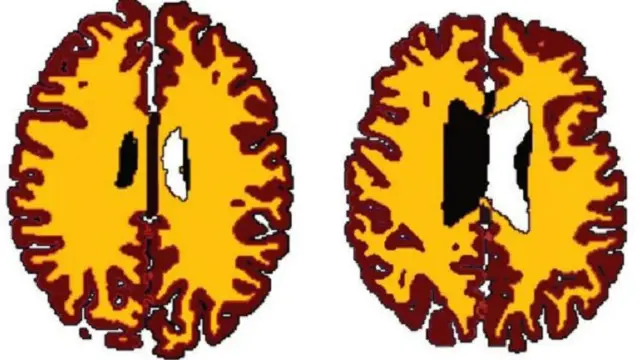

صدر الصورة، Dr Lisa Ronan

ووجدت النتائج التي نشرت في دورية علم أعصاب الشيخوخة، فروقا هامة في حجم المادة البيضاء في أدمغة الأشخاص الذين يعانون من زيادة الوزن مقارنة بالأشخاص الأقل وزنا.

وكانت المادة البيضاء في أدمغة زائدي الوزن أقل بكثير منها عند نظرائهم الأقل وزنا.